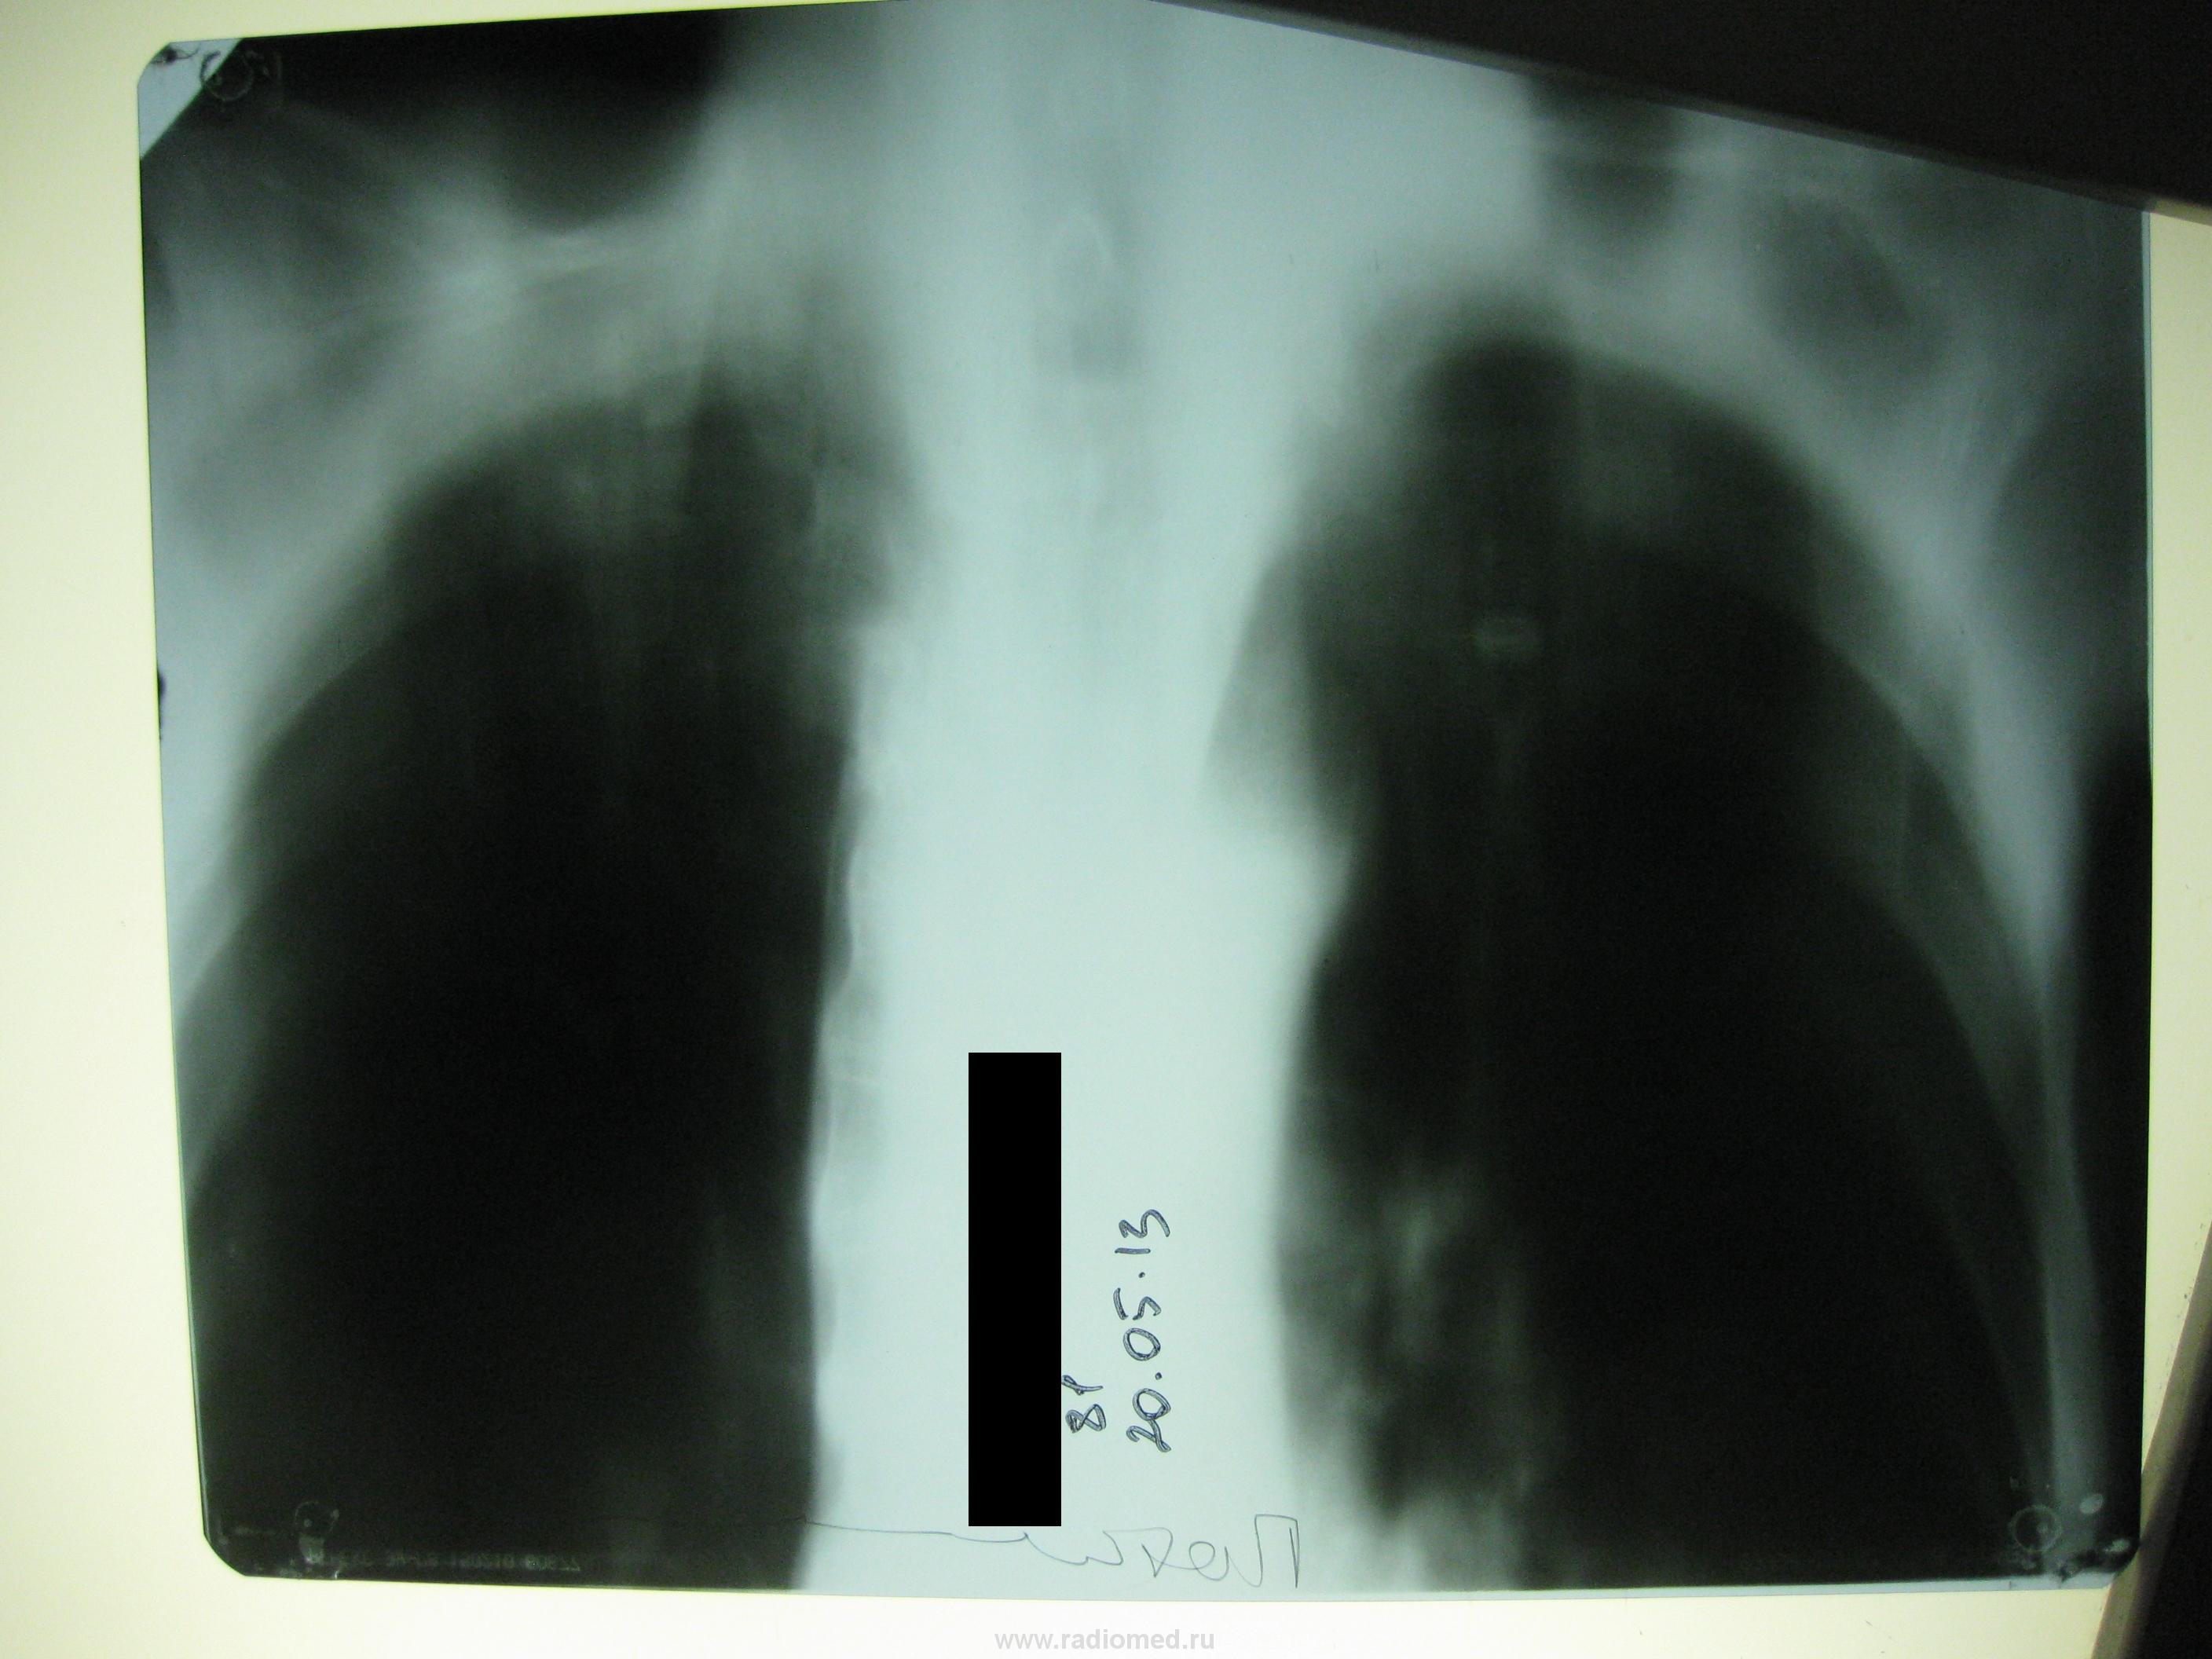

здравствуйте, уважаемые коллеги! Приехал в нашу ЦРБ сегодня дедушка из деревни, фельдшер пишет обострение хронического бронхита. Сам малоконтактен, говорит что кашляет, анализов пока никаких. Показались очаги справа на верхушке. Слева в нижней доле инфильтрация? Хотелось бы услышать ваше мнение. Спасибо!

По томограммам ничего не скажу, потому что ничего не видно (мне). А инфильтрация - она и есть инфильтрация (пока, во всяком случае). А клиника-то пневмонии есть? Если при такой инфильтрации её нет - подозрительно.

Слева пневмония.Остального увидеть нельзя.

Пневмония в 10ке слева.

я тоже думаю что S10

Левое легкое явно отличается по прозрачности от правого: и межреберные промежутки, и обеднение легочного рисунка. Боковой снимок - правый или левый?неясно.

Сделать бы Р-гр. левый бок и прямой снимок с захватом н\отд.

Мое мнение, что пневмония вторичная.

Я не по поводу предположений. Я по поводу хронического бронхита в рентгенологическом заключении вообще. Да и в частности - какой такой бронхит даст локальное изменение прозрачности легочной ткани? А ведь оно явно видно и на плохих представленых снимках. А если еще и без динамики - совсем нехорошо. Лучше бы, конечно, увидеть здесь качественные снимки в динамике, еще лучше - качественную томографию бронхиального дерева и зоны локальных изменений в легком ( в идеале - РКТ). Да и бронхоскопия не помешала бы (потом).

Не успел опередить Алексея Станиславовича.Если при такой картине нет динамики-дело тревожное.Если нет клиники-ещё тревожнее на тему онкологии.Если имеете возможность-дообследуйте.Приотсутствии динамики-не о бронхите разговор.